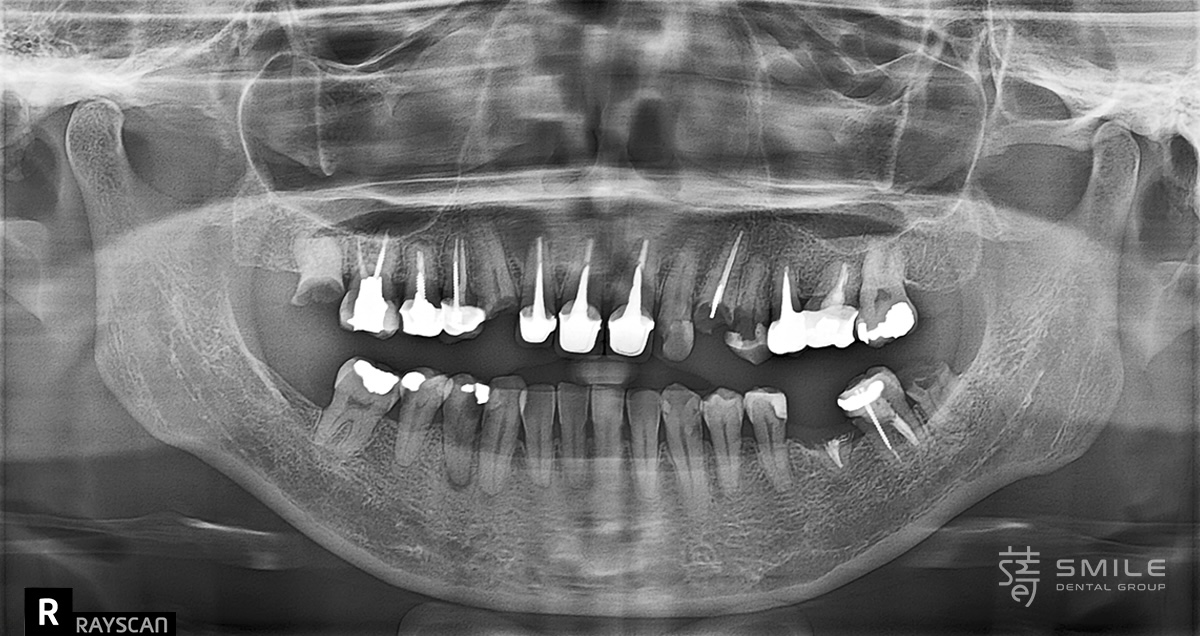

像許多曾被看牙經驗嚇到的病患一樣,陳太太長年對牙科懷有深深恐懼。牙齒出問題時,她總是一拖再拖,直到疼痛難忍才走進診間。當她來到蒔美牙醫諮詢全口植牙重建時,口腔狀況已相當複雜:多顆缺牙、大範圍蛀牙、根尖發炎、牙齒斷裂與舊假牙不密合,疼痛成了生活的一部分,吃飯也變得困難。更讓她難受的是笑容的流失,不再敢自在開口說話。

Like many patients who have been traumatized by dental experiences, Mrs. Chen had lived with a deep fear of the dentist for years. Every time a tooth caused pain, she would put off treatment until it became unbearable. When she finally came to Smile Dental for a consultation about full-mouth reconstruction, her oral condition was quite complex: multiple missing teeth, widespread cavities, root inflammation, fractured teeth, and ill-fitting old crowns. Pain had become a daily burden, and eating was a constant struggle. Even more disheartening, she had lost the confidence to smile freely or speak without hesitation.

陳太太的口腔問題多重且互相影響,紀醫師採取「先穩定環境、再全面重建」策略,分區塊、分階段逐步進行。此方式不僅有效控制風險,也讓癒合更穩定,減輕病患身心壓力,也是讓整體重建更有節奏,並達到最高品質的方式。

Because Mrs. Chen’s oral issues were multiple and interrelated, Dr. Ji adopted a “stabilize first, rebuild later” strategy, working in segments and phases. This approach not only controls risk effectively, but also ensures each stage heals reliably, reducing physical and mental stress, and giving the entire reconstruction a steady, high-quality rhythm.

第一階段 處理感染,打好重建基礎

Stage One: Clearing infection and laying the foundation

多顆牙齒因蛀蝕或牙根斷裂無法保留,先拔除並補骨,等待新骨生成;上顎後牙區進行上顎竇增高手術,增加骨高度。

可保留牙齒完成根管治療與牙套重做,密合不良的假牙亦更換,避免牙齦長期發炎。這一階段重點是徹底清除感染、建立穩固基礎,為後續重建鋪路。

Several teeth were too damaged or fractured to save, so they were extracted, and bone grafting was done to encourage new bone growth. In the upper molar area, a sinus lift was performed to increase bone height.

Teeth that could be preserved underwent root canal treatments and new crowns were fitted, while poorly sealed prosthetics were replaced to prevent chronic gum inflammation. This stage focused on eliminating infection and establishing a solid base for future reconstruction.